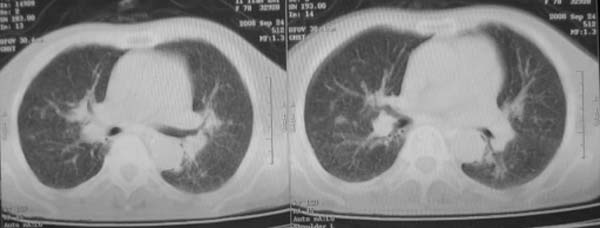

女,78岁,声嘶月余,否认有既往病史,有粉尘接触史10年。

矽肺

首先考虑尘肺.

矽肺。

双上肺结节融合影,周围有纤维条索影,结合粉尘接触史,首先考虑尘肺。双侧颈部有增大淋巴结,有声嘶表现,肺癌淋巴结转移不能排除。可结合颈部淋巴结活检。